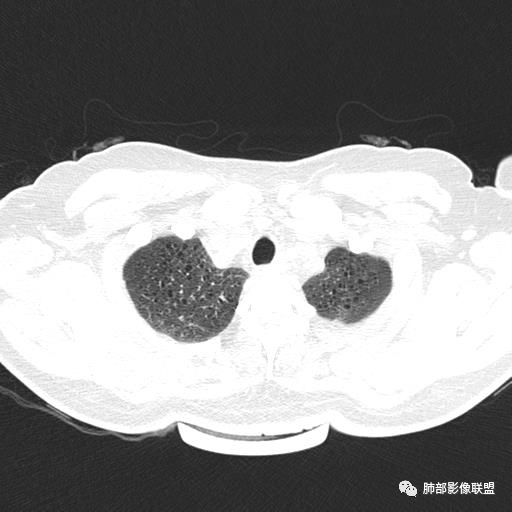

双肺弥漫囊腔,累及肋膈角,囊腔形态相对规则单一。

CT平扫示双肺弥漫分布大小不等囊状薄壁透光区,无内、中、外带分布差异,间质稍示增厚。拟LAM

双肺弥漫大小不一薄壁含气囊腔,囊间肺组织正常,正常肺背景,肺尖肺底受累;青年女性,气喘,支持LAM

CT表现:双肺弥漫大小不等的薄壁囊腔,囊壁<2mm,外形规则,血管影多位于囊腔周围,囊腔之间肺组织正常,随着疾病进展到晚期,囊腔变大、增多,不可胜数,囊腔可融合成较大的囊,与肺气肿相似,形成间质性肺纤维化。部分病例可出现结节影。